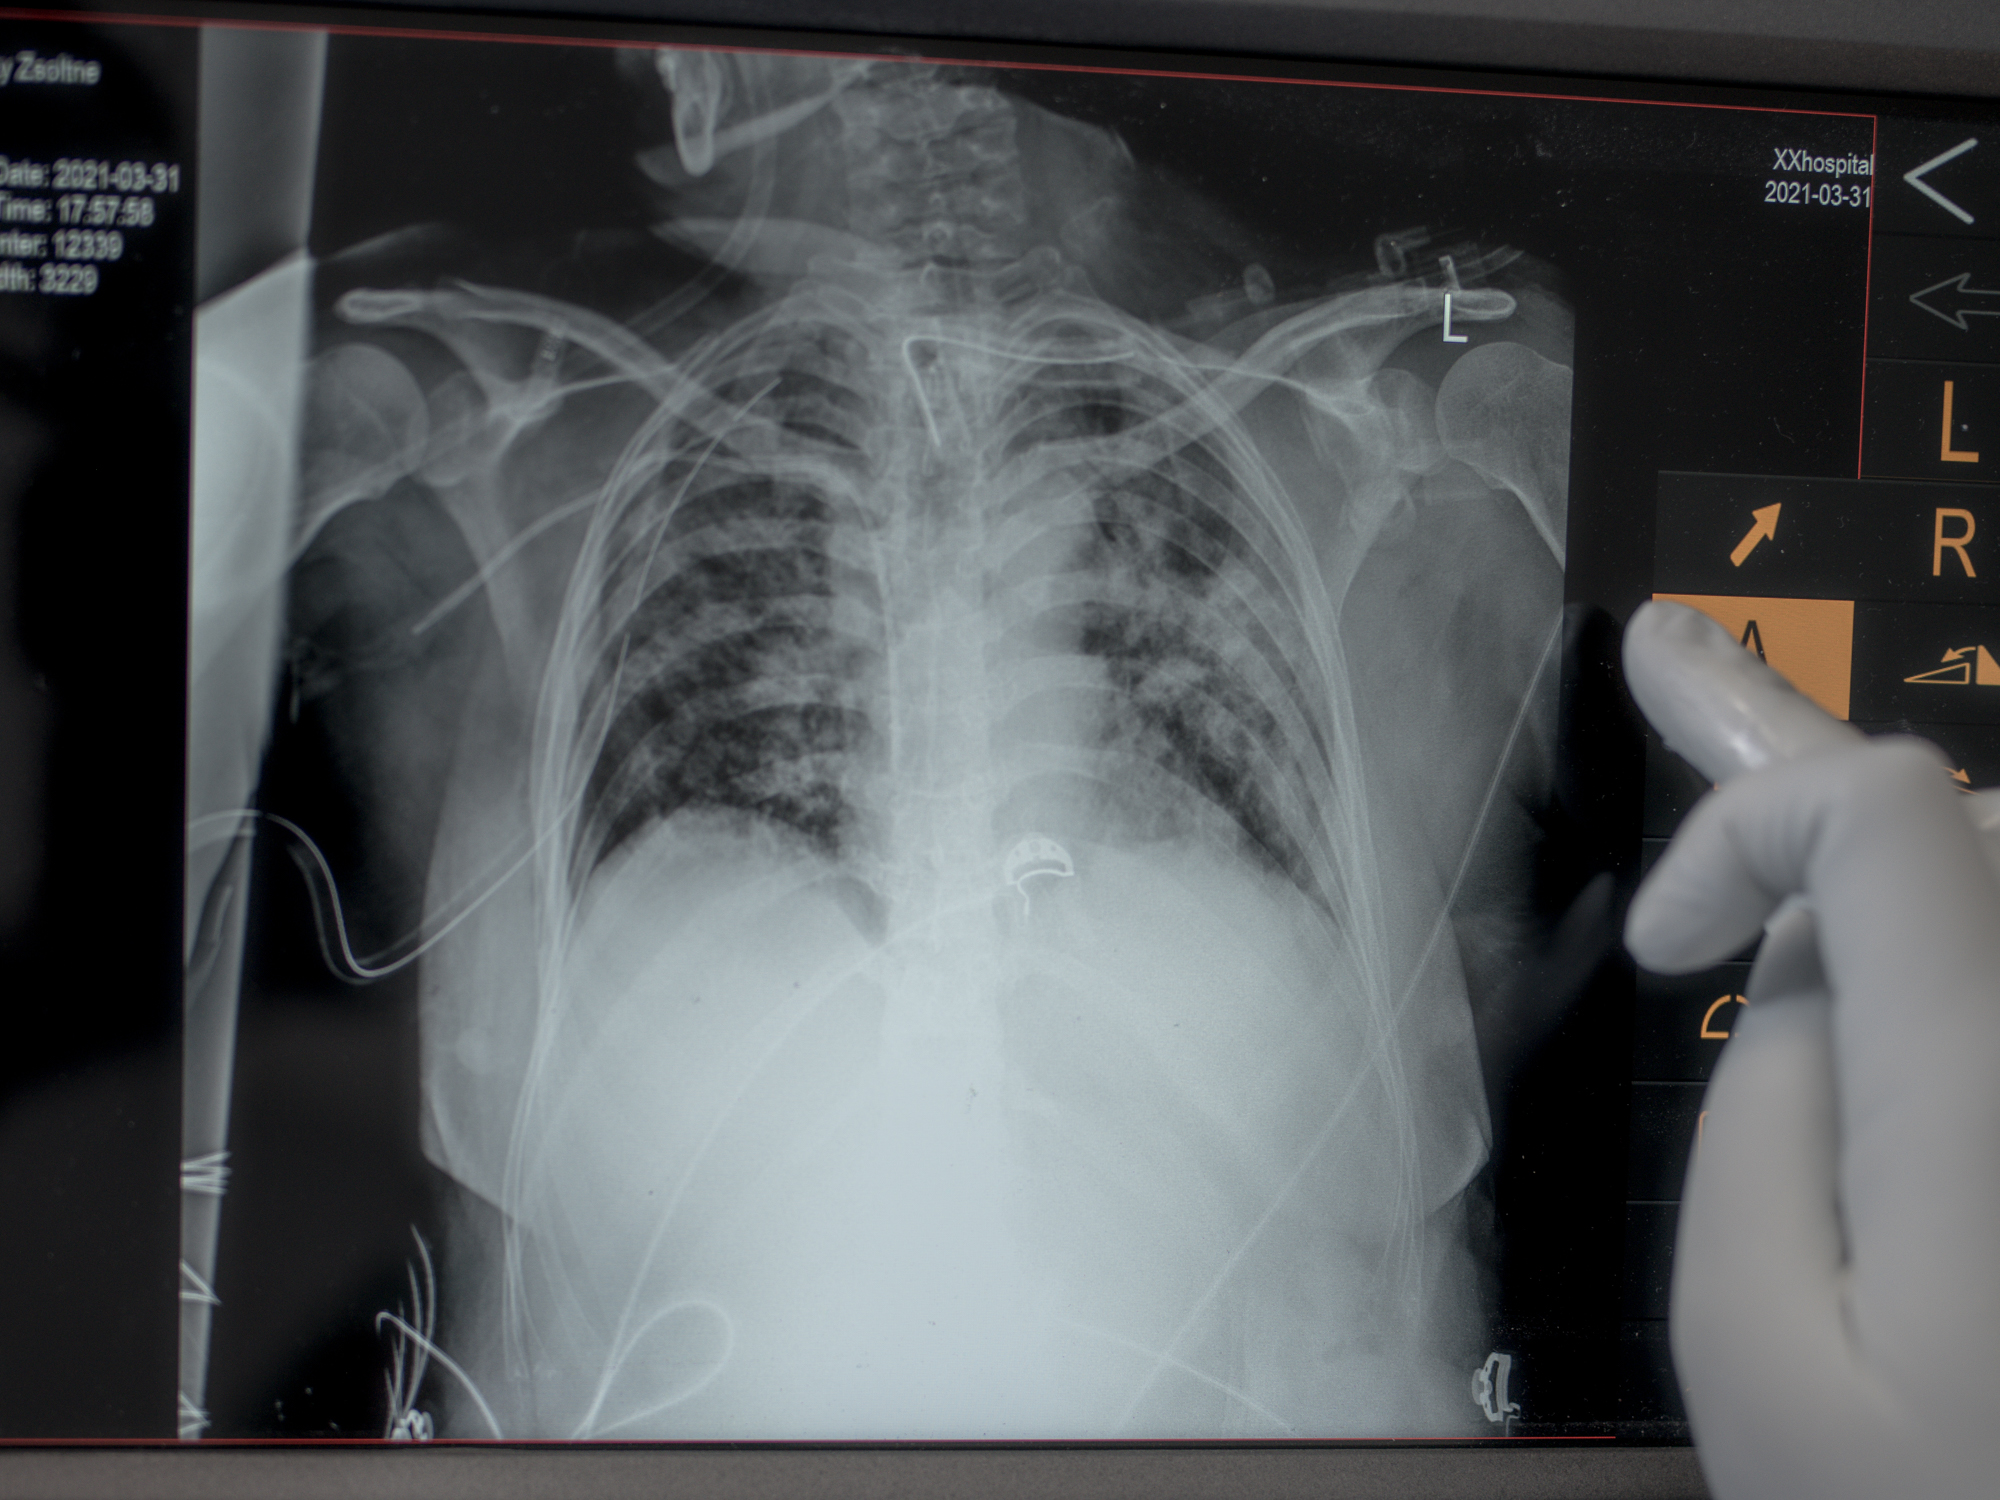

At the beginning of 2020 the world was confronted with one of the biggest challenges of our modern-day history. The COVID-19 pandemic redefined daily life for the entire country, including in the Uzsoki Street Hospital in Budapest, the capital city of Hungary. The true heroes of the year were doctors, nurses, and healthcare workers who battled the epidemic, risking their lives every day on the frontline under extremely demanding circumstances. Nearly 80 healthcare workers lost their lives due to the coronavirus in Hungary in the past few years. Among those who died were nurses, primary care physicians, gynecologists, chief physicians, and paramedics.

The Uzsoki Street Hospital has been functioning as the pandemic treatment center since the beginning of the first wave of COVID-19 infections, which resulted in various changes to the hospital’s daily operation. These changes were unfathomable a few years ago. The fight against the coronavirus at the Uzsoki Street Hospital eerily resembles the life-saving measures rendered on the battlefield: treating desperate patients in a life-threatening environment, fighting an invisible and deadly enemy, enduring extreme mental and physical fatigue, witnessing a high number of deaths. The number of deaths in Hungary has reached more than 40,000 since the beginning of the outbreak in the spring of 2020. This number is extremely high based on a comparison of coronavirus deaths in other countries relative to their population, putting Hungary in the top five most affected.